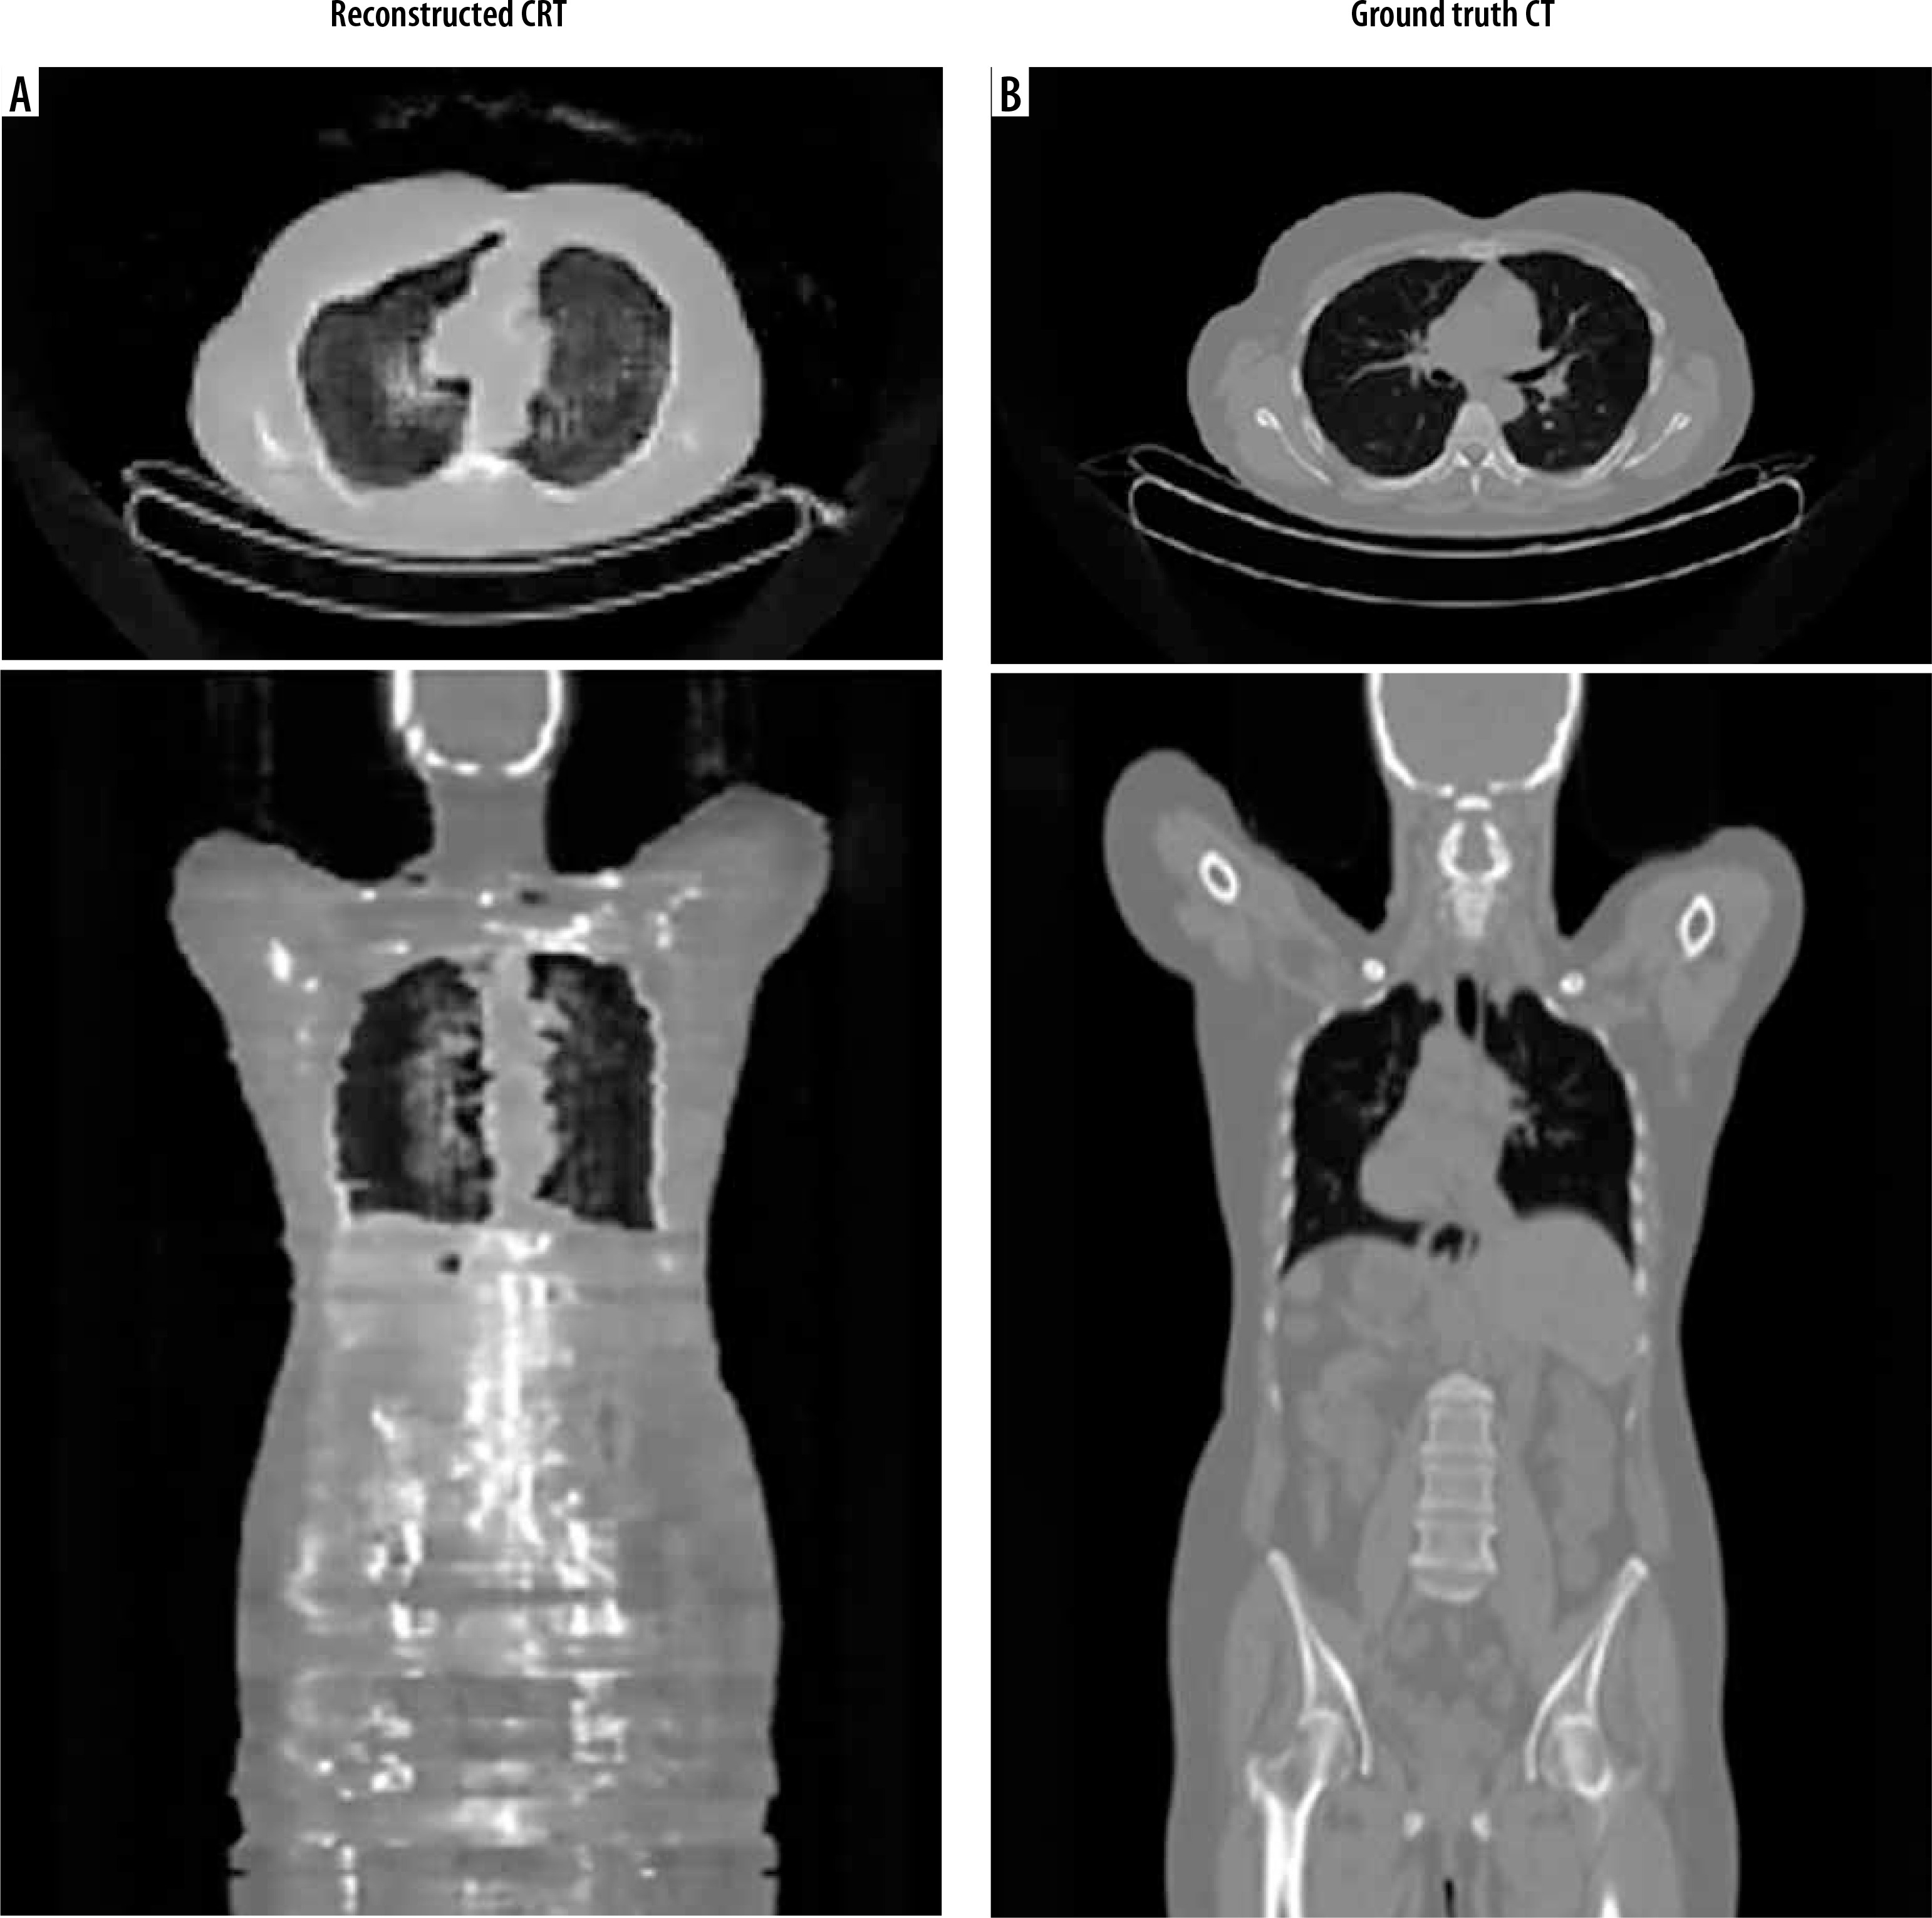

For CT reconstruction from non-attenuation-corrected PET images using the cycleGAN architecture, extensive hyperparameter tuning identified the optimal settings as a generator learning rate of 0.0001, discriminator learning rate of 0.00001, and batch size of 1. After training for 40 epochs, requiring 122 hours and 42 minutes, the network demonstrated the capability to generate reconstructed CT images from input non-attenuation-corrected PET data. While achieving reasonable overall image quality, the reconstructed CT images exhibited some difficulty precisely delineating bony structures compared to ground truth CT scans. Representative sample axial and coronal views of the network’s reconstructed CT outputs are provided, juxtaposed with the corresponding reference CT ground truth images (Figure 5).

Figure 5

Comparative axial and coronal images of reconstructed CT and ground truth. A) Pseudo-CT images reconstructed from the non-attenuation corrected PET input by the CycleGAN network. B) The expected ground truth CT images for comparison

Radiological evaluation was also based on HU levels in the reconstructed CT images. This evaluation aimed to calculate the HU levels for the whole body, lungs, bone, and liver in real and synthetic images and compare the results statistically. Unfortunately, the reconstructed CT images did not have the necessary quality for contouring the liver and bone, as evident in the reconstructed coronal image. The results are presented in Table 2.

In the reconstructed CT images, the lungs, as expected, showed negative HU levels due to air presence, and the statistical analysis between real and synthetic images showed no significant difference in lung HU levels. The same applies to the whole-body HU levels. The clear visual differences between reconstructed and real images, despite the closeness of the HU levels, suggest the inadequacy of this metric in assessing synthetic image accuracy.